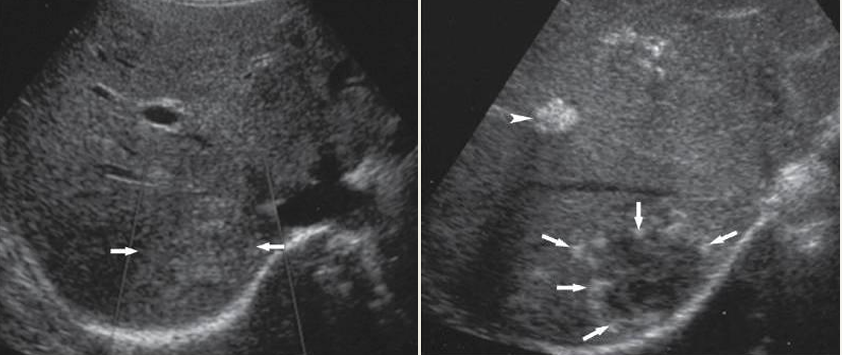

what lesion is this?

hemangiomas

patent TIPS

clotted TIPS

what is happening in this image?

rupture of microbubbles